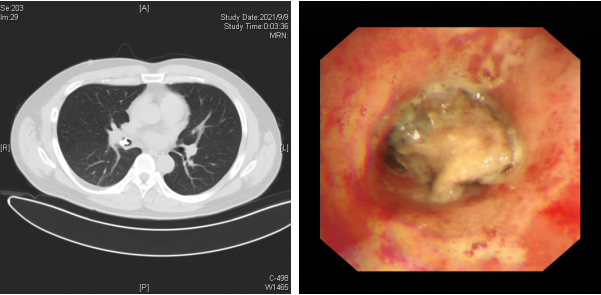

贴秋膘气管进异物 呼吸科紧急取出竟是肉骨

全身+局部 介入+灌注,清华长庚呼吸科治愈顽疾“肺毛霉菌...